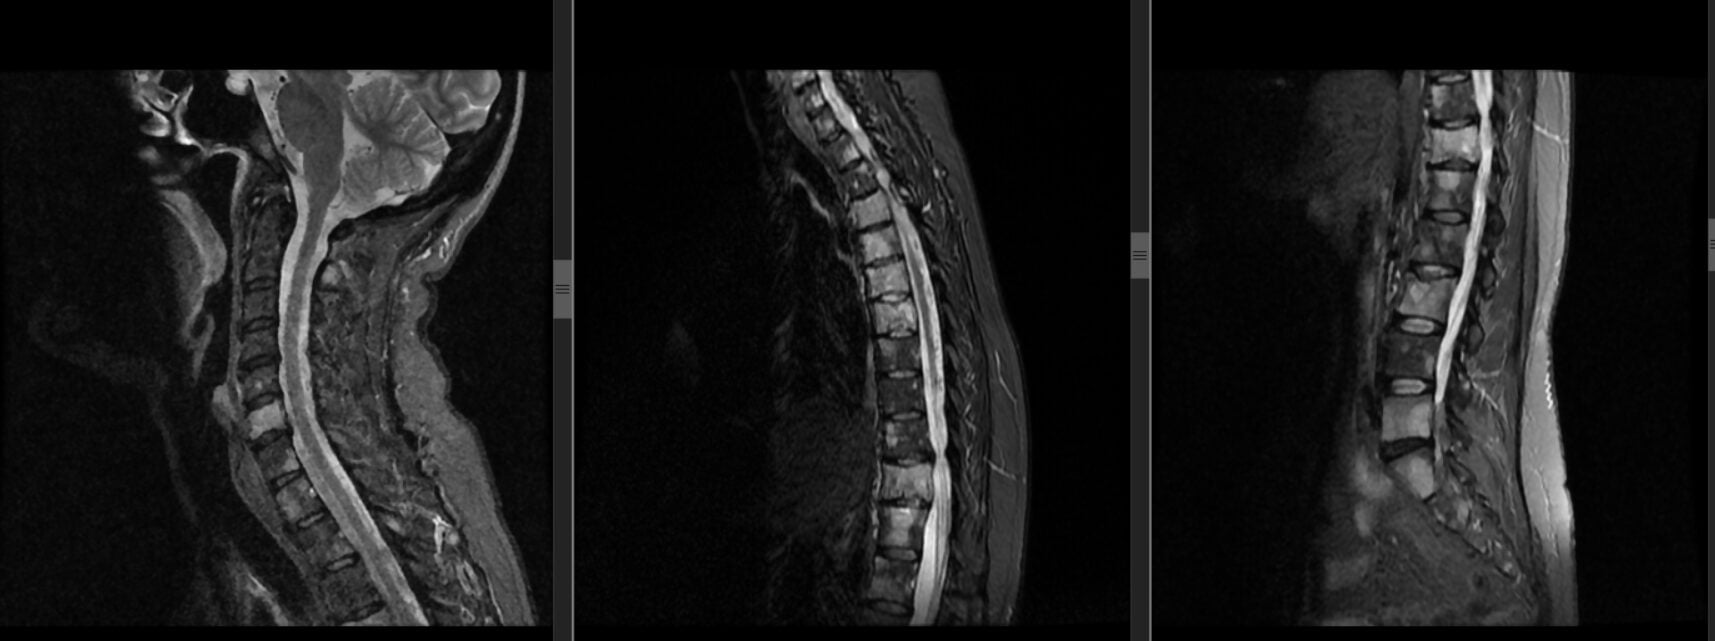

Recent a fost evaluată o pacientă în vârstă de 55 de ani, cunoscută cu cancer mamar, care s-a prezentat pentru dureri lombare persistente. Investigațiile efectuate au evidențiat metastaze osoase localizate în corpurile vertebrale, afectând trei niveluri diferite ale coloanei vertebrale.

Monitorizarea imagistică are un rol esențial în evaluarea pacientelor cu cancer de sân și simptome noi la nivelul coloanei vertebrale.

• rezonanța magnetică (RMN) a coloanei vertebrale, în special atunci când apar dureri persistente sau simptome neurologice.

În cazul prezentat, investigațiile imagistice au confirmat prezența metastazelor vertebrale. Dezvoltarea metastazelor în interiorul corpului vertebral determină fragilizarea progresivă a osului, crescând riscul de fracturi patologice, instabilitate spinală și compresie asupra structurilor nervoase.